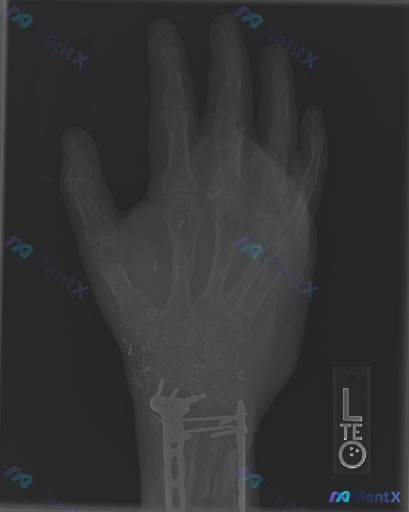

- 有左腕关节桡骨远端骨折术后史,目前内固定在位,可见骨痂生长

- 左手掌及腕部广泛分布有散在的细小金属高密度影

- 第3掌骨骨干中部至远端骨皮质不连续,骨结构模糊,可见不规则溶骨性改变与骨密度增高混杂表现,骨干呈膨胀性改变,边界不清,第3掌指关节间隙狭窄模糊,周围软组织明显肿胀